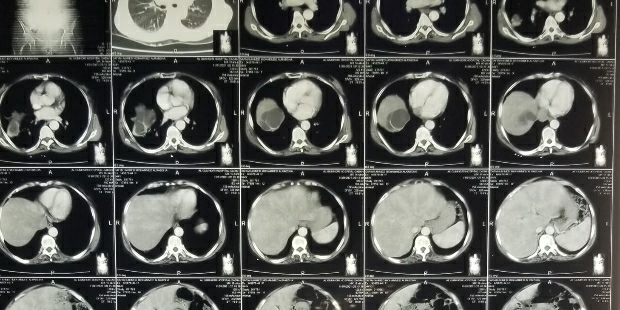

نجح اطباء هيئة المستشفى الجمهوري بمحافظة صعدة بحضور الدكتور / محمد الفيشي ، والدكتورة /اشواق الجنيد، وطاقم قسم العمليات، من إنجاز عملية جراحية استئصال اكياس مائية متعددة في تجويف البطن والحوض لمريض كان يعاني آلامًا شديدة في البطن بشكل مفاجئ، حيث تبين بعد عمل الفحوصات الطبية اللازمة ، وجود اكياس مائية كبير داخل البطن والحوض مع تجمع بعض السوائل، وتم بعد استكمال الفحوصات الطبية اللازمة التحضير بدقة للعملية واتخاذ جميع الاحتياطات اللازمة

وادخالة غرفة العمليات وتم بحمد الله استئصال الاكيس بالكامل دون انفجارها ،

في عملية استغرقت وقت قصير حيث أن هذه الحالة نادرة جداً.